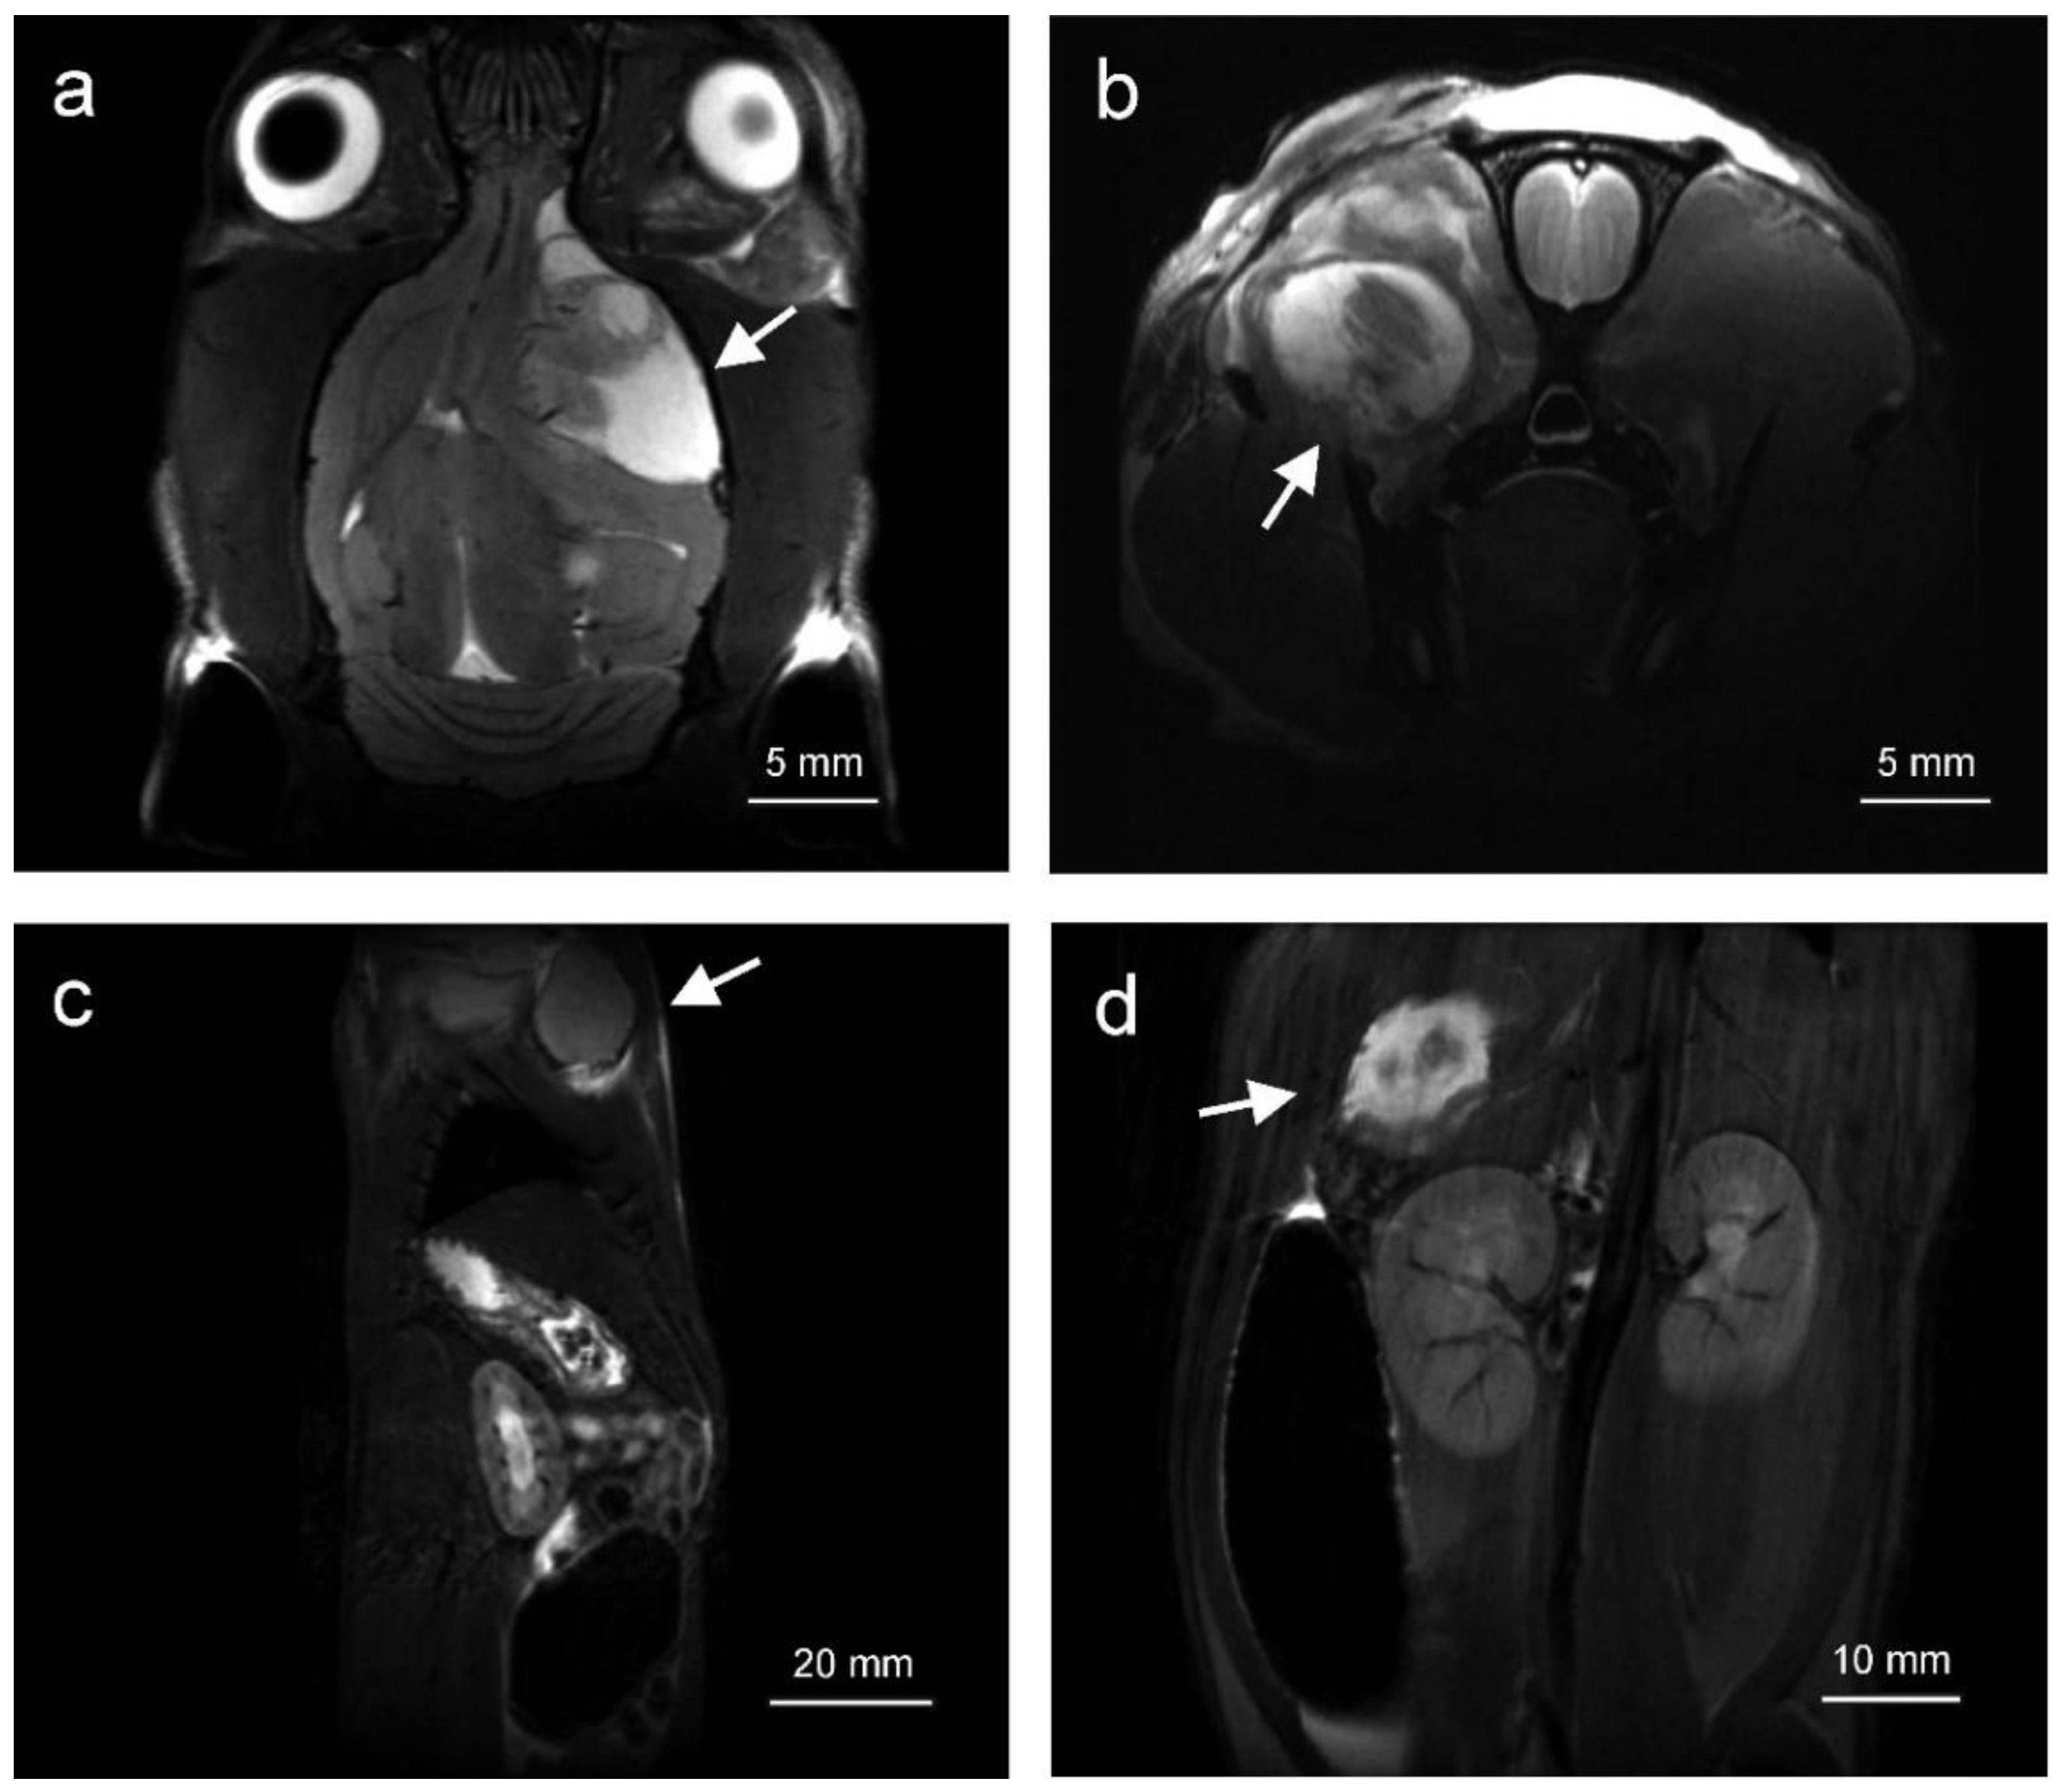

2.1. Tumors Localize in the Head and Neck, Extremities and Abdomen and Are Metabolically Active

4.2. Magnetic Resonance Imaging